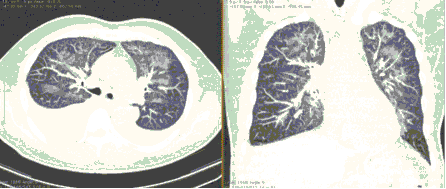

КТ имеет высокую чувствительность в выявлении изменений в легких, характерных для COVID-19. Применение КТ целесообразно для первичной оценки состояния ОГК у пациентов с тяжелыми прогрессирующими формами заболевания, а также для дифференциальной диагностики выявленных изменений и оценки динамики процесса. КТ позволяет выявить характерные изменения в легких у пациентов с COVID-19 еще до появления положительных лабораторных тестов на инфекцию с помощью МАНК. В то же время, КТ выявляет изменения легких у значительного числа пациентов с бессимптомной и легкой формами заболевания, которым не требуется госпитализация. Результаты КТ в этих случаях не влияют на тактику лечения и прогноз заболевания при наличии лабораторного подтверждения COVID-19. Поэтому массовое применение КТ для скрининга асимптомных и легких форм болезни не рекомендуется. При первичном обращении пациента с подозрением на COVID-19 рекомендуется назначать КТ только при наличии клинических и инструментальных признаков дыхательной недостаточности (SpO2 < 95%, ЧДД > 22).

3. Применение лучевых методов у пациентов с симптомами ОРВИ легкой степени тяжести и стабильном состоянии пациента, возможно только по конкретным клиническим показаниям, в том числе при наличии факторов риска, при условии достаточных технических и организационных возможностей. Методом выбора в этом случае является КТ легких по стандартному протоколу без внутривенного контрастирования или РГ при ограниченной доступности КТ. Использование УЗИ в этих случаях нецелесообразно. Применение КТ исследования в сроки ранее 3 - 5 дней с момента появления симптомов заболевания, а также при отсутствии клинических проявлений поражения бронхолегочной системы является нецелесообразным. Выполнение КТ целесообразно при наличии клинических и инструментальных признаков дыхательной недостаточности (SpO2 < 95%, ЧДД > 22), либо при дифференциальной диагностике с другим заболеванием.

4. Все выявляемые при лучевых исследованиях признаки, включая КТ-симптомы, не являются специфичными для какого-либо вида инфекции и не позволяют установить этиологический диагноз. Вне клинической (эпидемической) ситуации они не позволяют отнести выявленные изменения к пневмонии COVID-19 и дифференцировать их с другими пневмониями и невоспалительными заболеваниями. Данные лучевого исследования не заменяют результаты обследования на РНК SARS-CoV-2. Отсутствие изменений при КТ не исключают наличие COVID-19 и возможность развития пневмонии после проведения исследования.